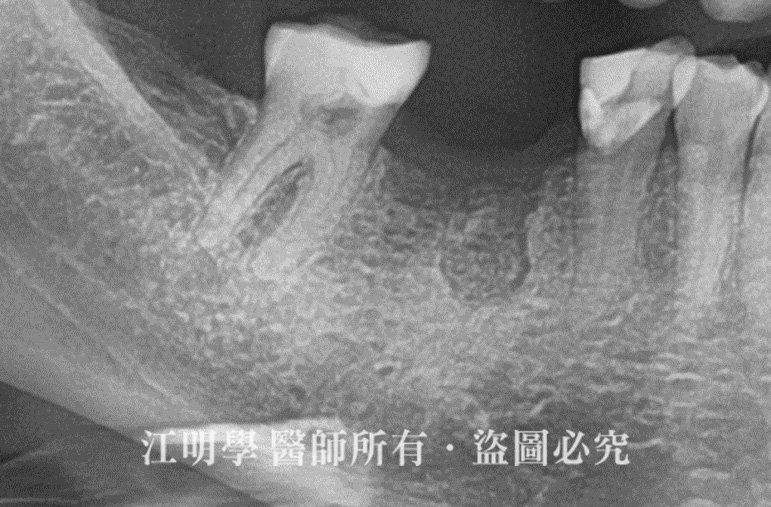

治療前X光